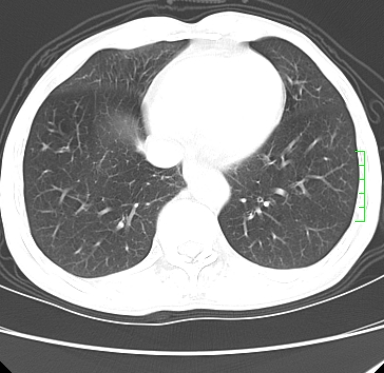

m,73y。膝关节疼痛伴双下肢水肿。入院常规胸片发现结节灶。增强为静脉期。

肿块周围可见局限性气肿,考虑肺癌可能性大。双肺上叶继发型肺结核。

指套征,强化明显,近侧肺组织局限性肺气肿,考虑支气管类癌,慢支、肺气肿、双上陈旧性tb、冠脉钙化。

1)考虑右肺下叶周围型肺癌。2)右肺上叶及左肺感染性病变(结核可能)。3)肺气肿。4)冠状动脉钙化。